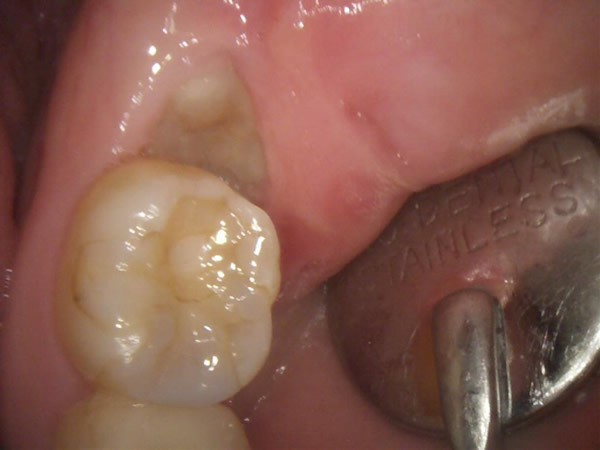

下の親知らずが歯ぐきから半分頭を出して生えている状態です。レントゲンで確認すると、親知らずがどのように生えているのかを確認できます。